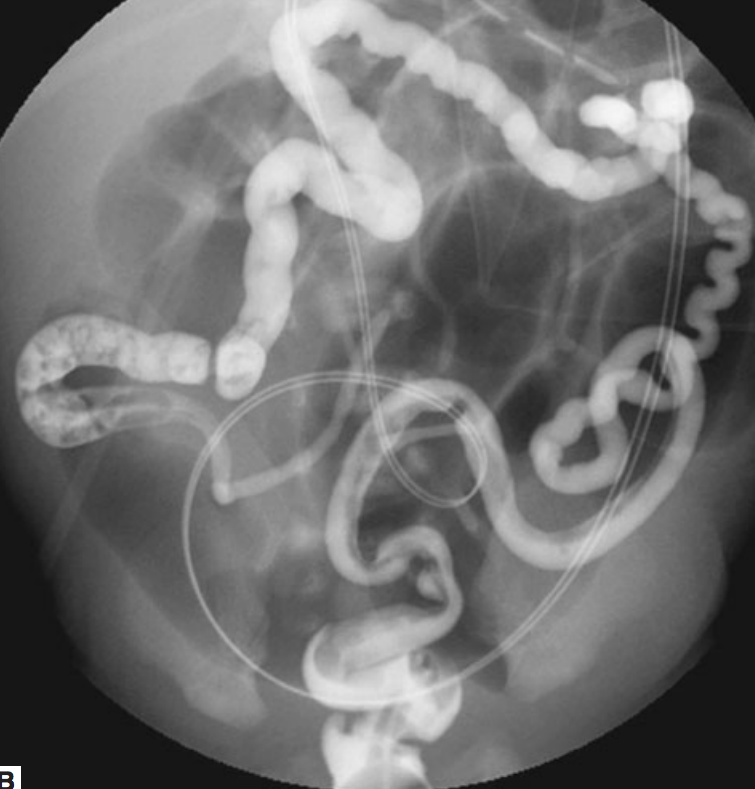

water-enema to diagnose and dissolve plug

90%: contrast enema to see transition point